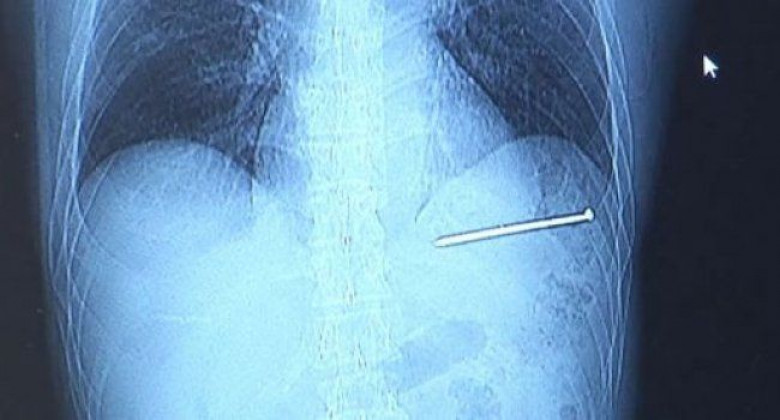

Տղամարդը պատահաբար մեխով իրեն «սրտի պիրսինգ» է արել. լուսանկարներ

Վիսկոնսին նահանգից տղամարդը, որը պատահաբար 9-սանտիմետրանոց մեխով իրեն «սրտի պիրսինգ» է արել, կարողացել է մինչեւ հիվանդանոց ինքնուրույն հասնել: Նա հաղթահարել է մոտ 20 կմ տարածություն՝ չգիտակցելով, թե դա որքան վտանգավոր է:

52-ամյա Դագ Բերգեսոնը բժիշկներին ասել է, որ սկզբում հազիվ է ուշադրություն դարձրել  կրծքավանդակի շրջանի վերքին: 9-սանտիմետրանոց մեխը մխրճվել է ուղիղ նրա սրտի մեջ: Տղամարդը շինարարական աշխատանքներ է կատարել՝ քար շարելով սեփական տանը, երբ դժբախտ դեպքը տեղի է ունեցել: Դագը մեխեր խփելու հատուկ սարք է օգտագործել, սակայն այն բավարար ուժով չի սեղմել պատին: Դուրս եկած մեխը ետ է թռչել ու հայտնվել ուղիղ տղամարդու կրծքավանդակի մեջ: Դագը սկզբում չի կռահել, թե վնասվածքը որքան ծանր է: Մի քանի րոպե անց նա, այնուամենայնիվ, հասկացել է, որ ավելի լավ է մեխն ինքնուրույն չհանի եւ մեքենայով հիվանդանոց է գնացել, որը տնից 20 կմ հեռավորության վրա էր:

Դագն ասել է, որ սրտի մեջ մխրճվելու ճանապարհի կեսին մեխն, այնուամենայնիվ, սկսել է ուժեղ ցավ պատճառել: Հիվանդանոցում տուժողին անմիջապես շրջապատել են բժիշկներն ու բուժքույրերը, եւ նա անընդհատ փորձել է կնոջը հաղորդագրություն ուղարկել, որ նա իրեն նոր հագուստ բերի, սակայն հեռախոսը համառորեն տեքստում ինքնաուղղումներ է կատարել՝ այն իմասատազուրկ դարձնելով:

Մի շարք թեստերից ու փայտացման դեմ ներարկումներից հետո Դագին ուղարկել են այլ բժշկական կենտրոն, որտեղ նրան սրտի բաց վիրահատություն են կատարել: Վիրահատությունը 1,5 ժամ է տեւել, եւ վիրաբույժները սրտի միջից մեխը հաջողությամբ հեռացրել են՝ համոզվելով, որ շրջակայքի հյուսվածքները լրջորեն չեն վնասվել:

Վիրահատությունը կատարած բժիշկ Ալեքսանդր Ռոյթշթեյնը լրագրողներին ասել է, որ իր հիվանդի բախտն անասելի բերել է: Մեխն ընդամենը մի քանի միլիմետր հեռավորությամբ է անցել կարեւոր արտերիայից, ըստ որում՝ նա վնասվածքը ստացել է սրտի զարկի հենց այն փուլում, որը Դագին ողջ մնալու հնարավորություն է տվել: